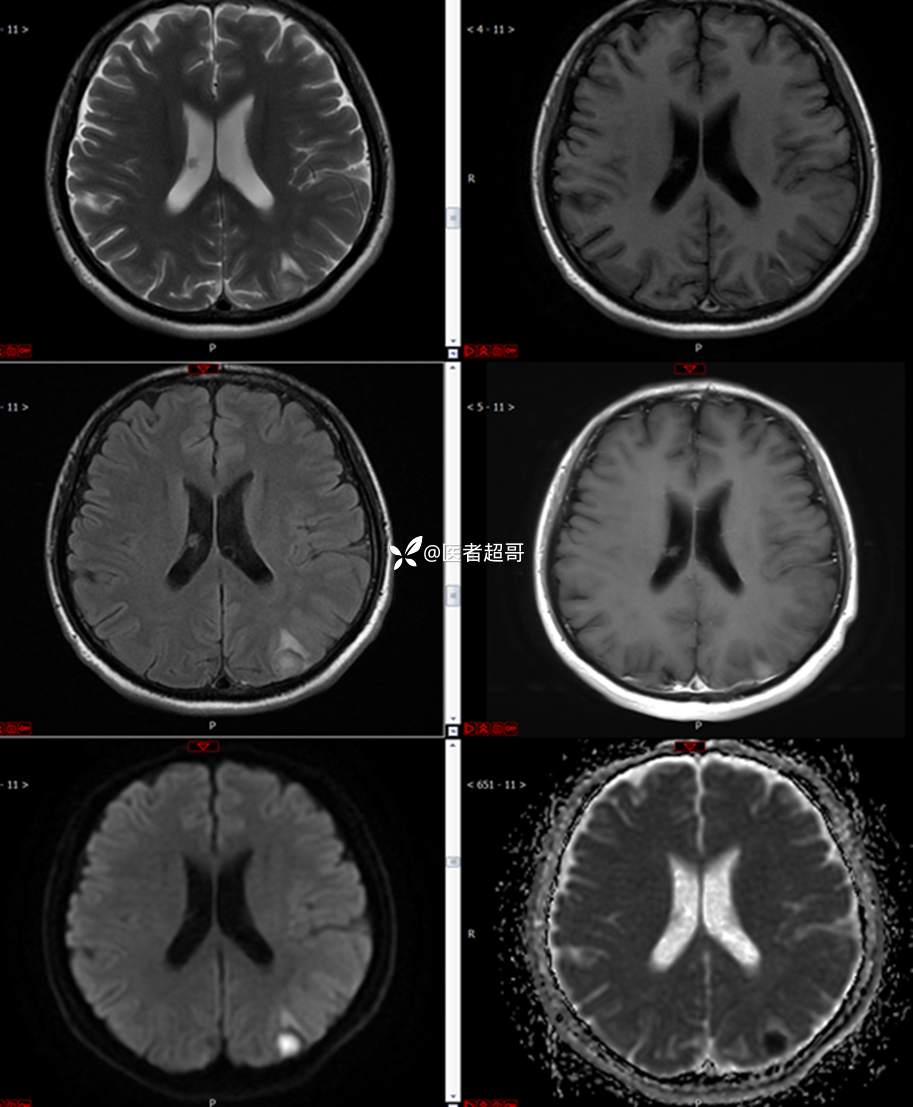

【影诊笔记773】头痛、头晕10天,CT、MRI齐全,请高诊!

主 诉:头痛、头晕10天

现病史:患者10天前无明显诱因感头痛、头晕,伴记忆力减退,无恶心、呕吐,无肢体抽搐及肢体活动不灵等,于我院就诊,行颅脑MR示颅内多发占位,现患者为求进一步治疗于我院就诊,以“颅内占位”收入我科。患者目前神志清,精神可,饮食、睡眠正常,体重无明显变化。

既往史:既往急性肝功能衰竭病史.